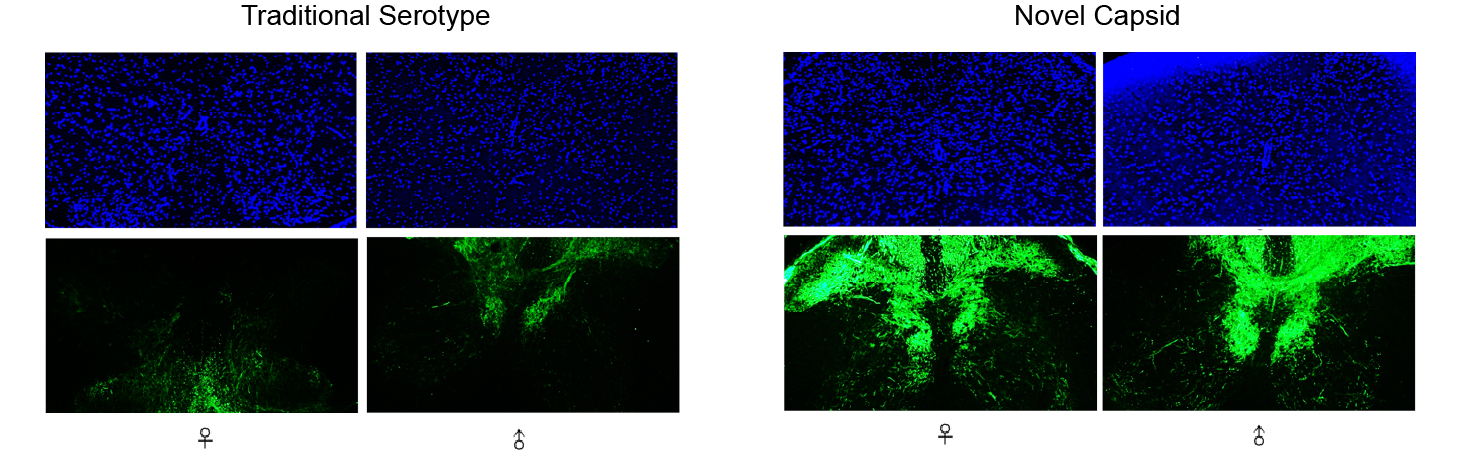

云舟生物采用衣壳进化筛选方法后的新型AAV衣壳。AAV转导小鼠颈椎,对比衣壳优化前的传统血清型AAV与优化后的新型衣壳AAV的转基因(CMV>EGFP)递送效率。